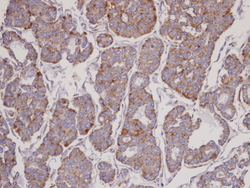

Supportive validation

- Submitted by

- Signalway Antibody LLC (provider)

- Main image

- Experimental details

- Immunohistochemical analysis of paraffin-embedded Thyroid Ca, using FBL6 antibody at 1: 100 dilution.